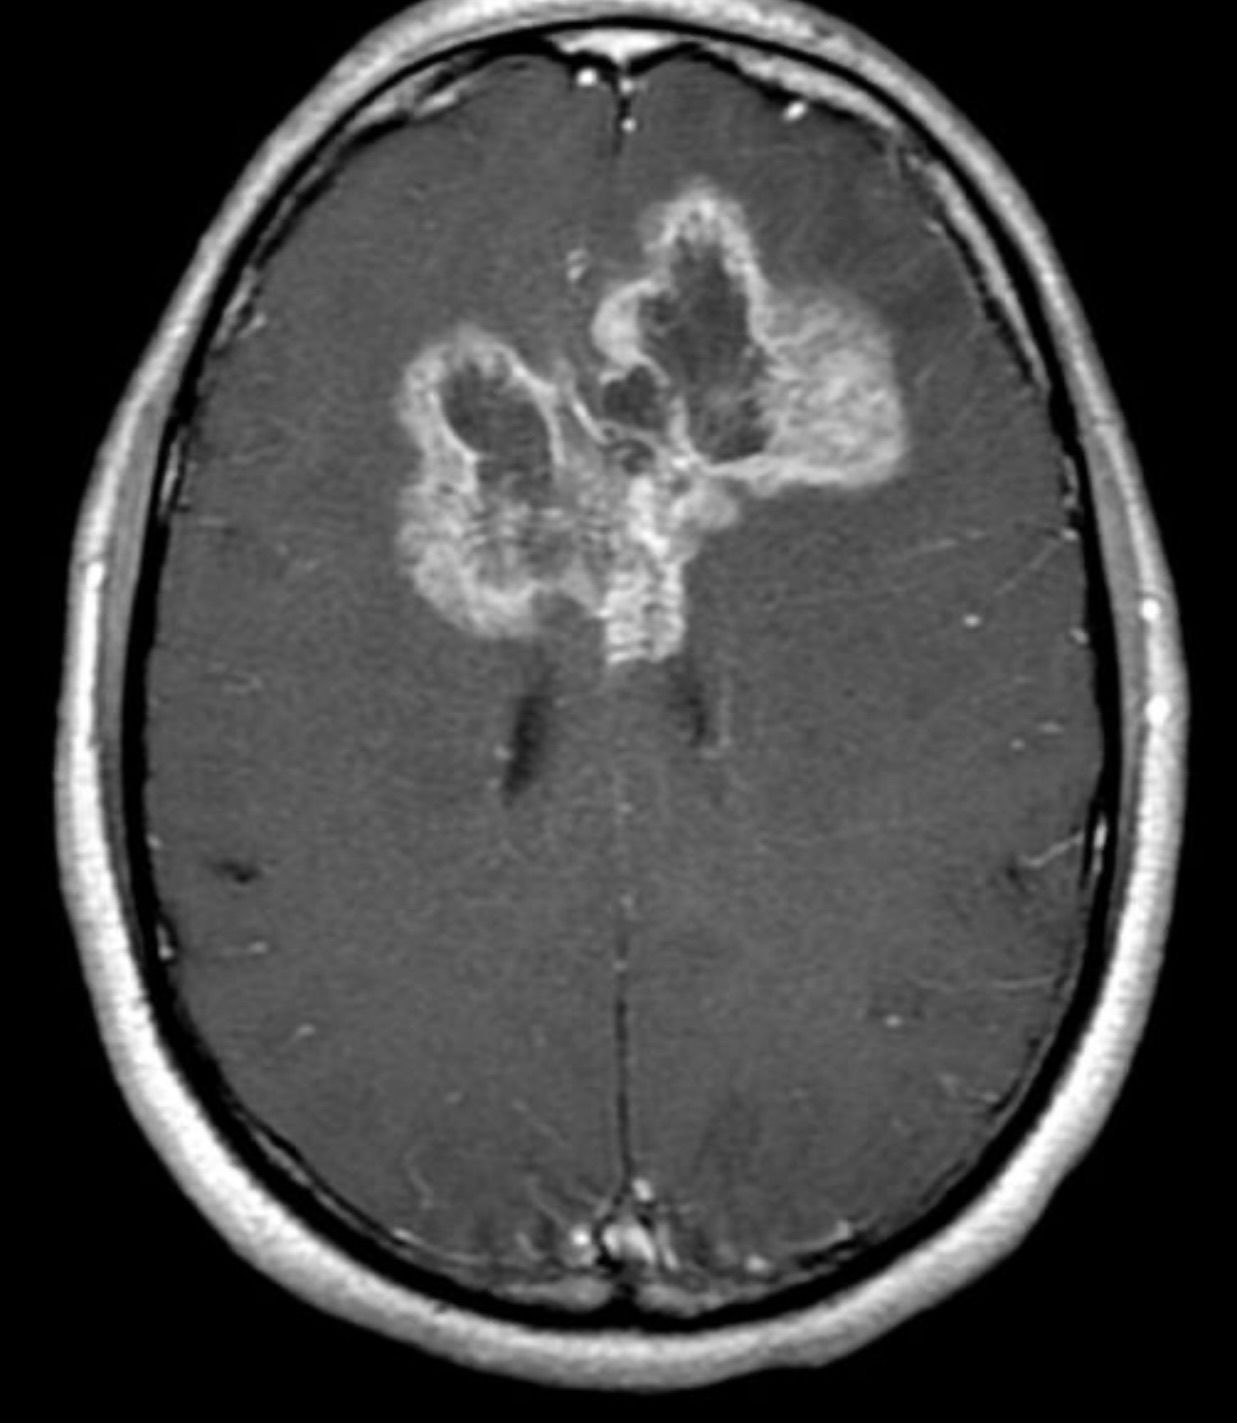

Imaging depicts a large butterfly glioma. This is seen when a GBM is able to cross over to the contralateral hemisphere by crossing the corpus callosum (midline). A GBM is a primary WHO grade IV intra-axial brain tumor. It is highly infiltrative and a craniotomy is usually performed. Unfortunately, prognosis is not the greatest and chemotherapies include Temodar (temozolomide) and Avastin (bevacizumab). Temodar does not seem to be effective for a good margin of patients if they have an unmethylated mgmt promoter.